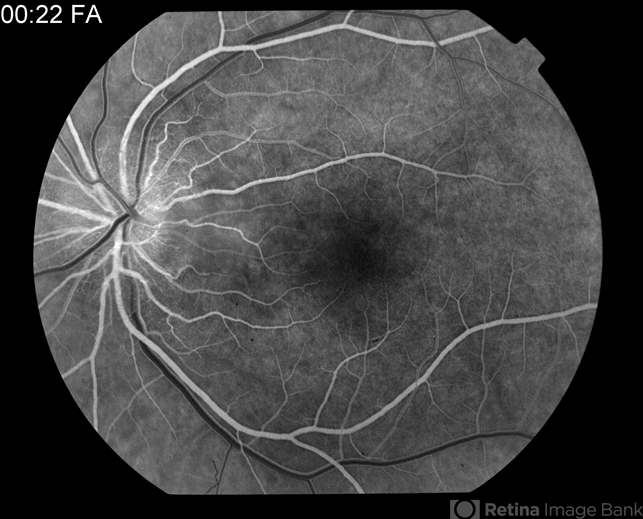

By Raj K. Maturi, MD

Midwest Eye Institute & Retina Partners Midwest

Co-author(s): Thomas A. Ciulla, M.D. Midwest Eye Institute - Uploaded on Oct 18, 2012.

- cat scratch retinitis, Bartonella bacteria

- Tom Steele, CRA

Fundus camera

Topcon 50dx